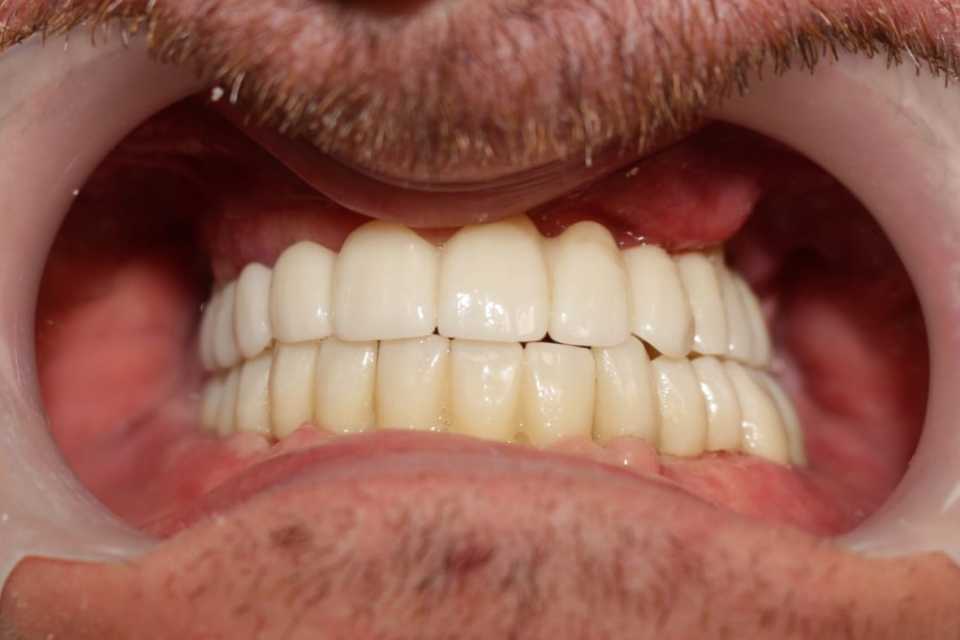

Lucrări fixe cimentate la nivelul maxilarului din ceramica pe zirconiu

Reabilitarea orala funcțională și estetică, s-a realizat cu ajutorul unei lucrări fixe cimentate la nivelul maxilarului din ceramica pe zirconiu și a 3 lucrări din ceramica pe zirconiu fixe cimentate la nivelul mandibulei.